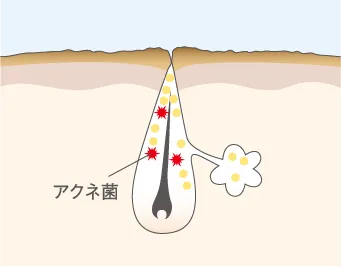

アクネ菌が繁殖し炎症に

毛穴に溜まった皮脂を栄養分としてアクネ菌が繁殖して炎症が起きる。赤く腫れている状態。触れると痛い場合も。